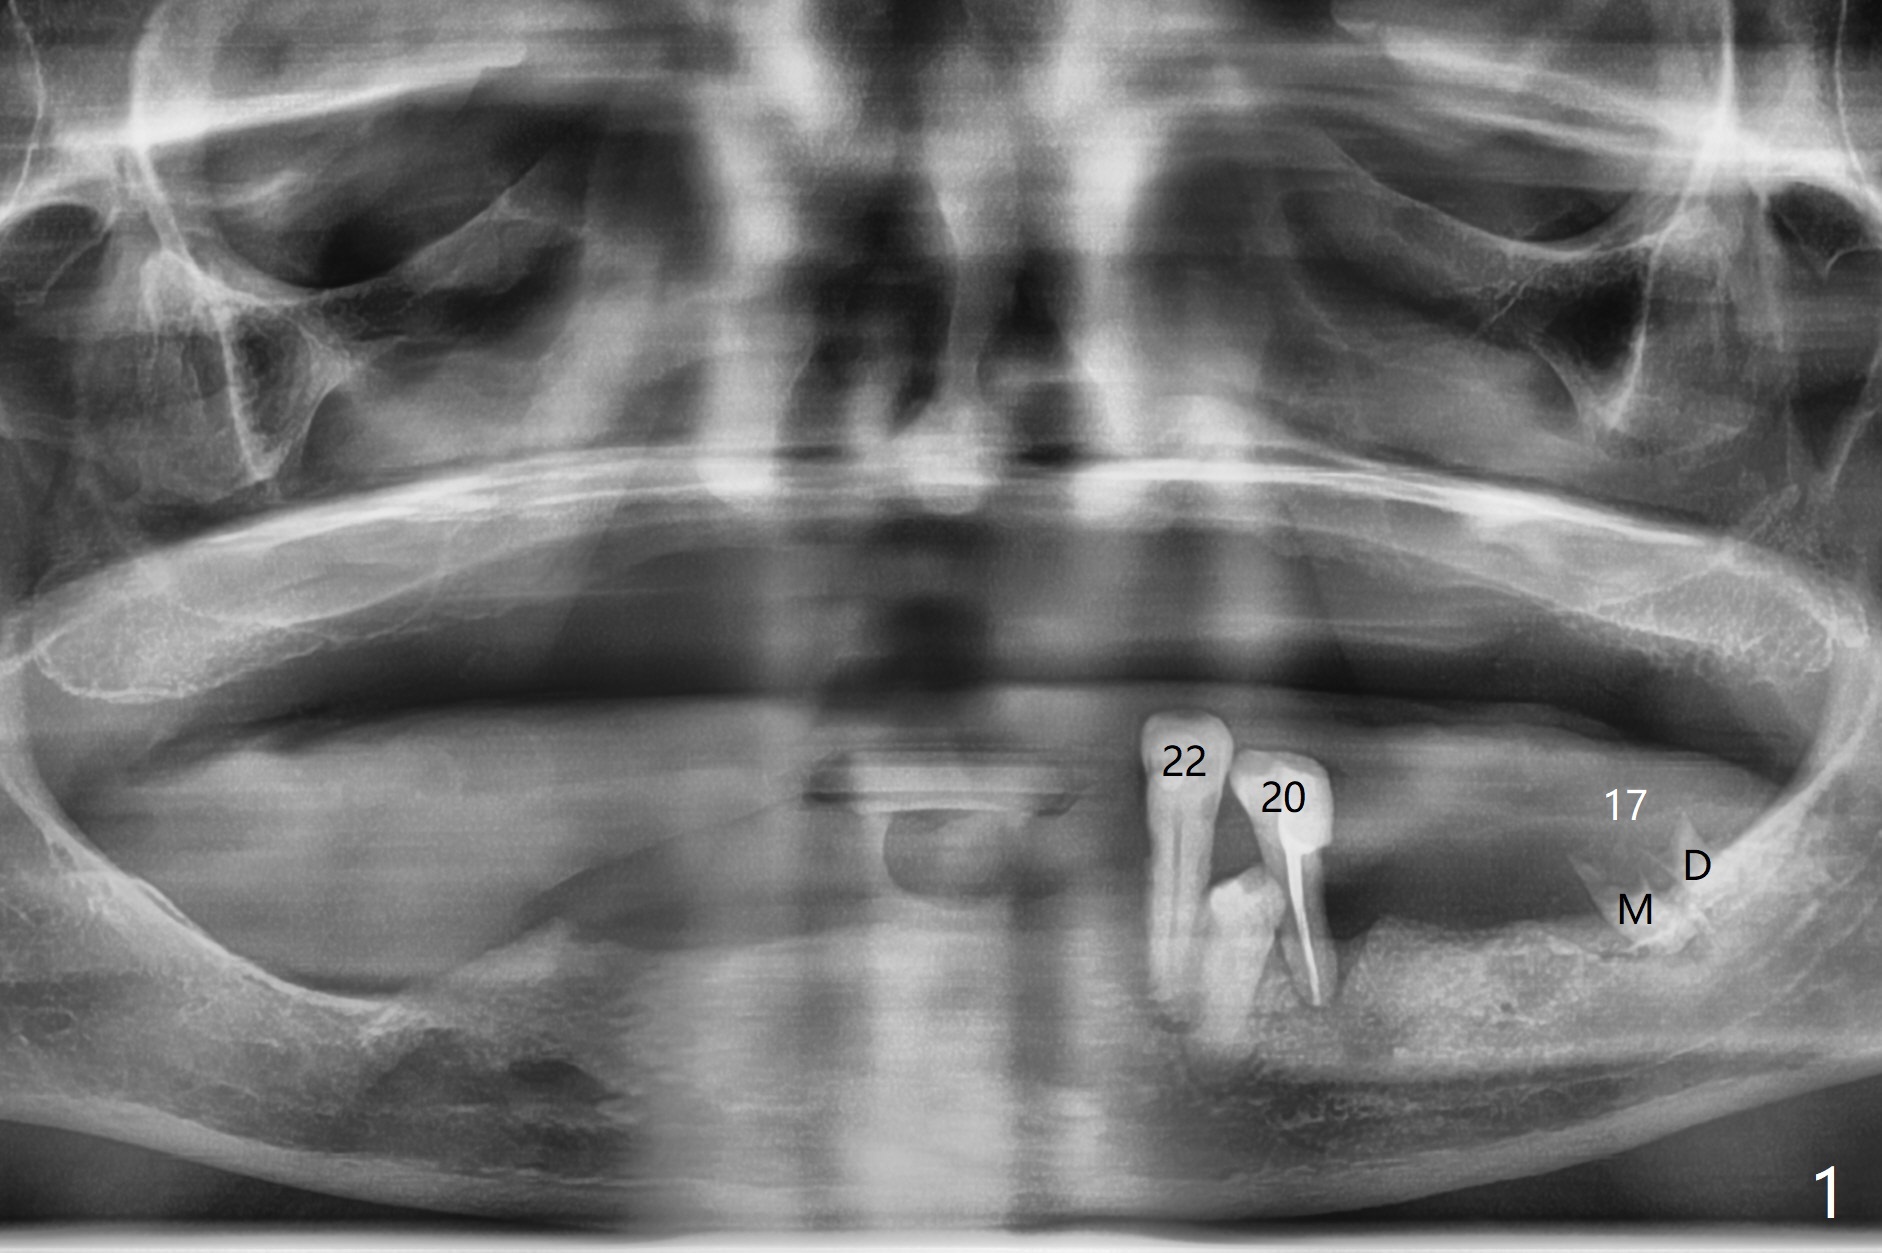

A 84-year-old man (uncontrolled diabetes) requests extraction of terminal teeth (#17, 20-22) for complete denture (Fig.1-3). He does not have finance for implants now. After extraction and debridement, 1 cc of Bond Apatite is applied to the sockets (Fig.4-6). The sockets at #20-22 are primarily closed with 4-0 PGA (Fig.7), while that of #17 with 4-0 Chromic gut suture over Osteogen Plug (a type of Collagen Plug, Fig.8). PGA sutures remain in place (Fig.9,10), while Chromic Gut ones dissolve 7 days postop (Fig.11). The ridge at the extraction sites remains robust 2 months postop (Fig.12). The sockets seem to remain radiopaque 2 months postop (Fig.13).